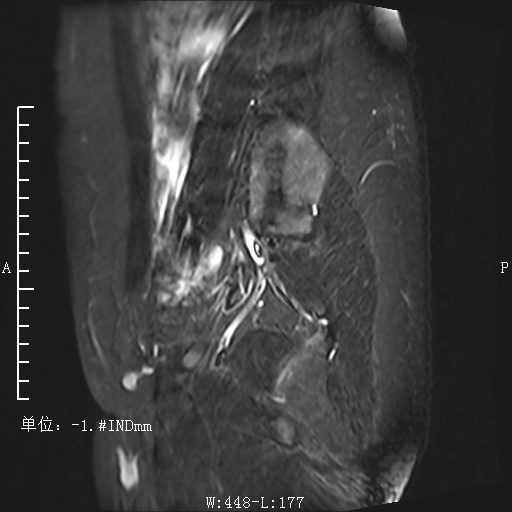

T2压脂矢状位

影像表现:子宫右后方见卵圆形软组织肿块影,与子宫后缘密切相连,病灶边缘清晰,病灶呈T1低信号T2低信号为主,其内夹杂少许散在斑片状T2高信号区,增强扫描病灶呈明显强化,与子宫肌层强化类似。盆腔未见明显肿大淋巴结,盆腔见片状压脂明显高信号影。

影像诊断:子宫浆膜下肌瘤。

MRI表现: 是发现和诊断子宫肌瘤最敏感的方法。在T1WI上,子宫肌瘤的信号强度类似子宫肌;然而在T2WI上,典型肌瘤呈明显低信号,边界清楚,与周围子宫肌信号形成鲜明对比。本例病灶与子宫后缘关系密切,病灶边缘清晰,T2呈较低信号,且增强呈明显强化,均符合较典型子宫肌瘤。